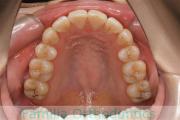

- ≫治療後

上顎

下顎

前歯の関係など

右側

正面

左側